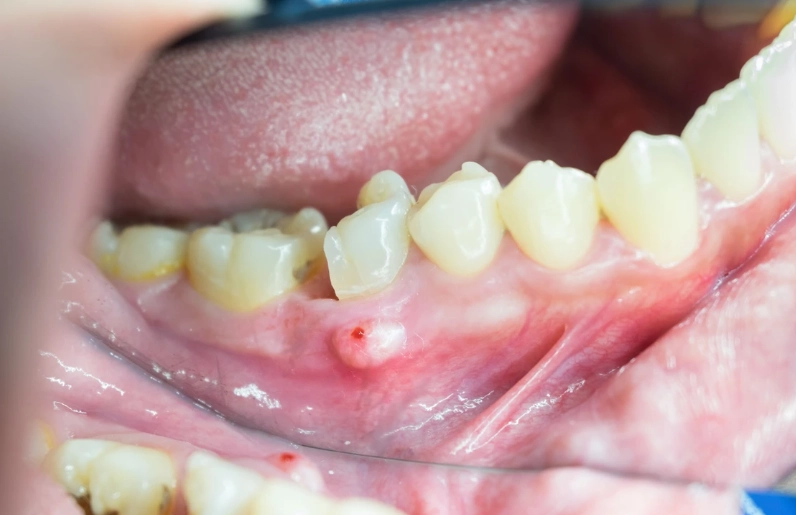

The specific code is K04.7 - Periapical abscess with sinus. Now, the 'with sinus' part confuses everyone at first. In dental terms, a 'sinus' here doesn't refer to your nasal sinuses. It means a sinus tract – a small, channel-like opening that the abscess creates to drain pus, often appearing on the gum as a pimple-like bump called a 'parulis' or 'gum boil.' This is the body's attempt to relieve pressure.

Then comes the clinical exam. They'll visually check the tooth and gums, looking for cavities, large fillings, cracks, or that tell-tale gum boil (sinus tract). They'll gently tap (percuss) on several teeth. The infected one will often feel exquisitely tender to this tapping. They might use a cold test (a quick shot of cold air or a cotton pellet with a freezing agent) on the tooth. A dead tooth won't feel the cold at all, while a dying one might have a prolonged, painful response.

But the real star of the show is the dental X-ray, specifically a periapical radiograph. This small, targeted X-ray shows the entire tooth from crown to root tip and the surrounding bone. A healthy tooth root is surrounded by a thin, uniform black line (the periodontal ligament space). With a periapical abscess, the dentist looks for a dark area (radiolucency) right at the tip of the root. This represents the bone loss caused by the infection. Sometimes it's a small, pinpoint dark spot; other times it's a large, ragged area. This radiographic evidence, combined with the symptoms and clinical tests, confirms the diagnosis.